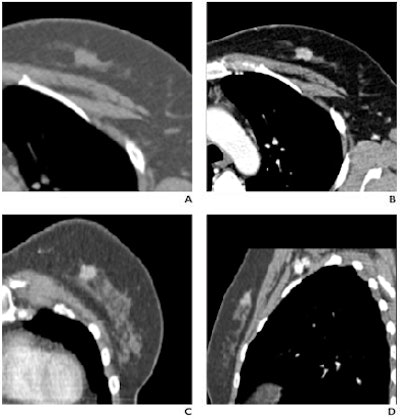

![]() |

| Fifty-two-year-old woman with invasive ductal carcinoma in left breast. (A and B) Dynamic MDCT images at baseline (A) and one minute (B) after contrast administration depict an irregular lesion with homogeneous enhancement; evaluation of time-attenuation curve showed washout pattern. (C and D) Coronal and sagittal multiplanar reconstructions one minute after contrast administration show lesion in A and B located in upper left quadrant of breast, approximately 2 cm behind nipple. |